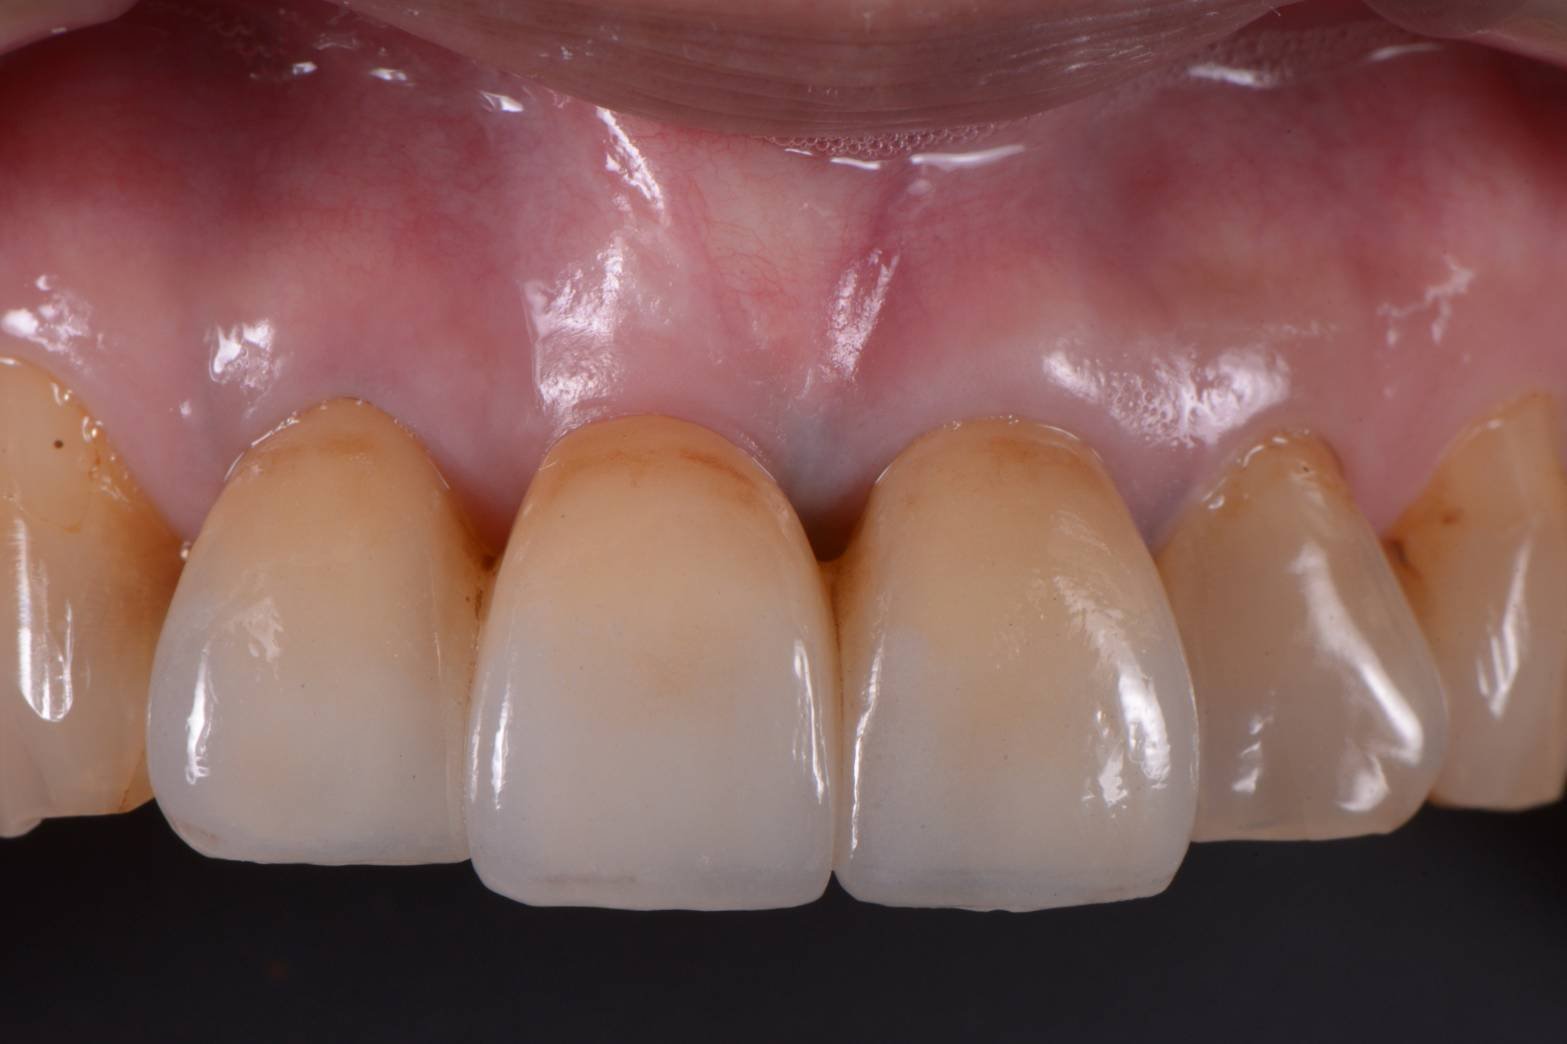

さて、どこの歯が欠損しているでしょうか??

このように歯があるように見せるためのセラミックの形態をオペイドポンティックと呼びます。

オベイドとは卵円型という意味で、歯肉の形態もそのような形になっています。

審美治療は奥が深い!!

本当に遣り甲斐のある分野です。